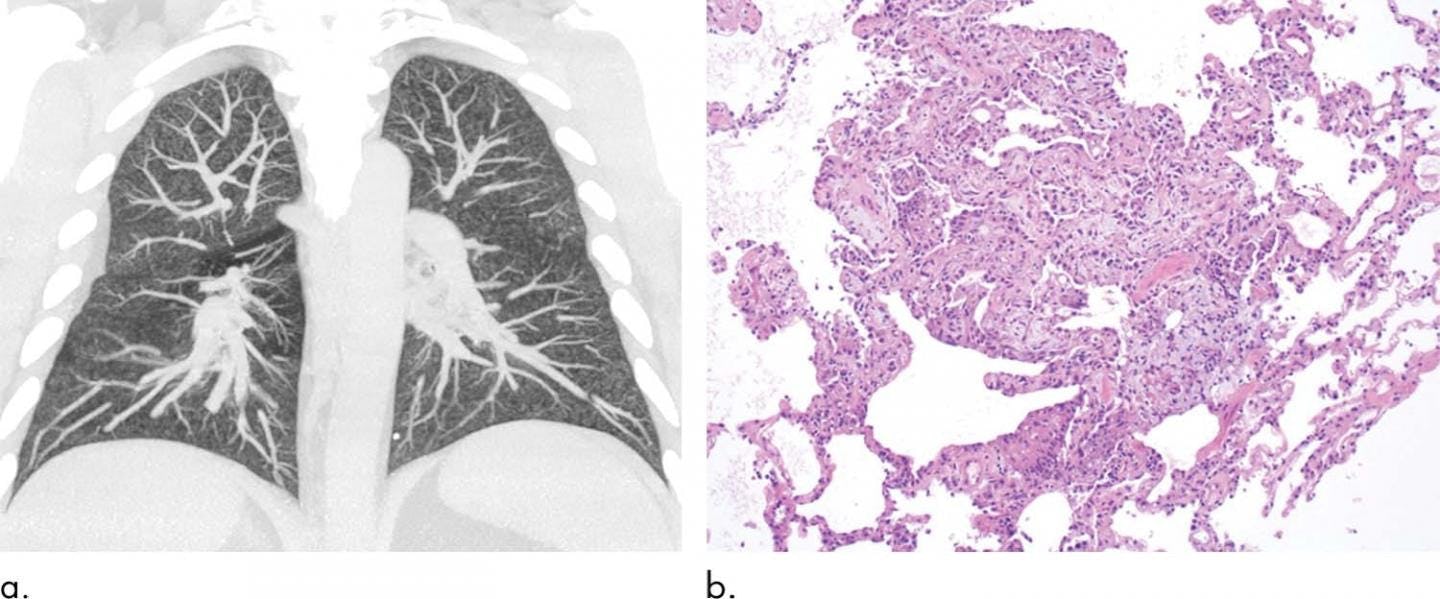

"The lungs bear a very close resemblance to what we see in workers where an industrial accident has occurred, with a toxic chemical spill or toxic fume exposure, or perhaps a poisonous gas exposure," the study's senior author, Brandon Larson, told Inverse at the time.

"It could explain the chemical pneumonitis observed in patients," he says.